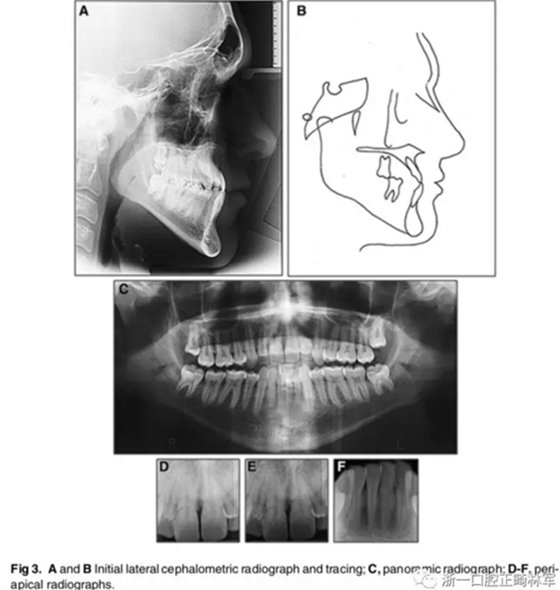

X片示:III類頜骨關(guān)系(ANB,-4°;Wits值,-10mm);上切牙前突、唇傾,下切牙內(nèi)縮(1:NA, 8mm、35°; 1:NB, 4mm、15°;IMPA, 77°);綜合考慮咬合平面角、下頜平面角、Y軸角,判定為水平生長型;McNamara分析示,上頜相對顱底后縮(Co-A, 88mm; A-NPerp, 4mm),下頜相對顱底前突(Co-Gn, 135mm; Pog-Nperp, 10mm),上下頜骨不調(diào)(Co-A–Co-Gn, 47mm);此外,患者4個第一前磨牙缺失。

影像學(xué):全景片示:牙根平行度可。頭顱側(cè)位片及疊加圖示:顯著的骨性、牙性改變;其中,最大的改變?yōu)樯舷骂M位置關(guān)系,改變了7mm;由此帶來的改變?yōu)锳NB角從-4°變?yōu)?°,Wits值由-10mm變?yōu)?1.5mm,上頜突度減?。ˋ-NPer,3mm),上下頜不調(diào)改善(Co-A-Co-Gn,41mm),從而使側(cè)貌更為平直;下頜磨牙遠(yuǎn)中移動,無伸長、傾斜,反映了下頜整體的遠(yuǎn)中移動;上下切牙傾角糾正(1:NA,7mm、25°; 1:NB,4.5mm、20°; IMPA,78°),從而改善了在基骨中的位置。